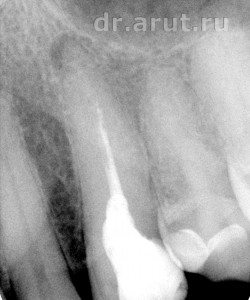

Пациен С. обратился в стоматологическую клинику с жалобой на боль в 23 зубе, усиливающуюся при накусывании. Изучение анамнеза заболевания, благодаря наличию истории болезни пациента с записями за последние 5 лет, установило, что в 2010 году 23 зуб был лечён по поводу обострения хронического периодонтита.

- Хронический периодонтит (Rg-графия 2010-го года)

5 лет назад, на момент обострения хронического периодонтита, канал уже был запломбирован, и врач-стоматолог попытался его распломбировать. Но к сожалению попытка не увенчалась успехом. В итоге канал был запломбирован на 2/3-3/4 длины (проходимая часть) форфенаном и гуттаперчиевыми штифтами. После лечения наступила 5-летняя ремиссии, закончившаяся в настоящее время и приведшая к очередному обострению хронического периодонтита.

Объективно: Зуб изменён в цвете. На окклюзионно-дистальной поверхности пломба, занимающая более 80% поверхности. Перкуссия болезненная, ЭОД выше 100µА. Во время ренгенологического исследования в области верхушки корня 23 зуба обнаружен участок просветления с нечёткими контурами размером 3-4 мм.